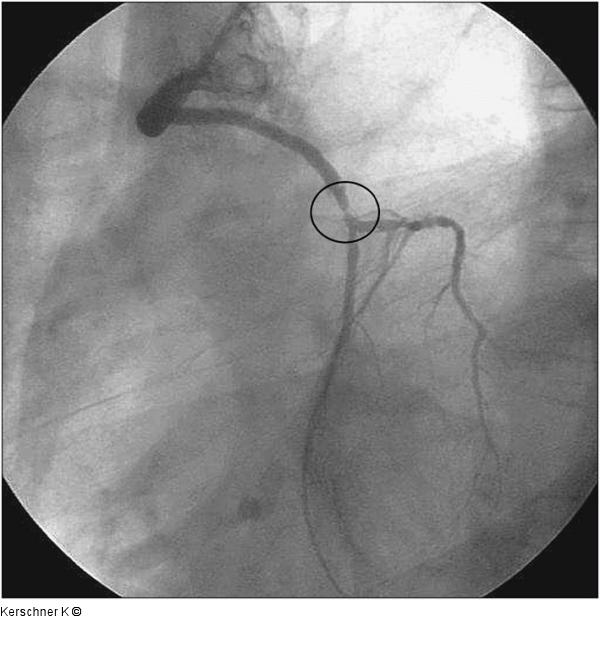

Abbildung 2: Aortokoronarer Venenbypass - LAO-Projektion Wie Abbildung 1 - LAO-Projektion |

Abbildung 2: Aortokoronarer Venenbypass - LAO-Projektion

Wie Abbildung 1 - LAO-Projektion |